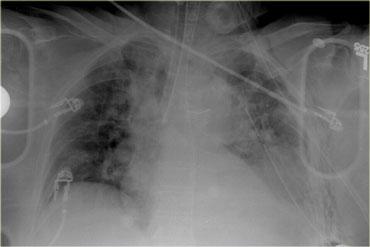

Bên trái là phim X-quang ngực của một tài xế 79 tuổi có thắt dây an toàn, bị tai nạn ô tô.

Ban đầu bệnh nhân không đáp ứng tại hiện trường.

Bệnh nhân được chuyển từ bệnh viện tuyến ngoài sau khi đã được đặt các ống dẫn lưu.

Hãy quan sát hình ảnh bên trái và mô tả các dấu hiệu.

Sau đó tiếp tục.

Điều đầu tiên bạn nhận thấy là ống nội khí quản đang nằm trong phế quản gốc phải.

Ống dẫn lưu màng phổi có vị trí phù hợp.

Ống thông dạ dày qua mũi đi xuống và cuộn lại trong dạ dày.

Trung thất trên trông có vẻ giãn rộng và bờ không rõ nét, do đó chắc chắn cần phải được đánh giá thêm.

Ở vùng phổi dưới trái, bờ cơ hoành không rõ nét và có hình mờ.

Điều này có thể do nhiều nguyên nhân như tràn máu màng phổi, đụng dập phổi, vỡ cơ hoành hoặc tổn thương lách.

Vì vậy, dựa trên phim X-quang ngực, chúng ta lo ngại về khả năng tổn thương động mạch chủ, đụng dập phổi và tổn thương cơ hoành, lách và thận trái.